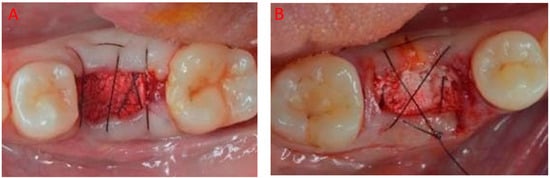

2.1. Surgical Protocol